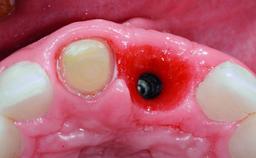

Replacement of a Missing Upper Left Central Incisor: Late Placement of an RC Bone Level Implant, CAD/CAM Zirconia Abutment

A healthy 37-year-old female patient was referred for a consultation on the replacement of missing tooth 21 with an implant-supported restoration. She stated that several years previously the tooth had been traumatically avulsed following a motor vehicle accident. The tooth was replaced with a three-unit fixed partial denture (FPD) immediately afterwards. Over time, she became disillusioned with the FPD and looked for a different option, including orthodontic therapy. She presented still in her orthodontic appliances, with the pontic sectioned free from the FPD but attached to the archwire. Her orthodontist felt that orthodontic treatment had been successfully completed, but nevertheless referred her before removing the appliances in case adjustments were necessary.

| Bone Volume | Deficient horizontally, allowing simultaneous augumentation |